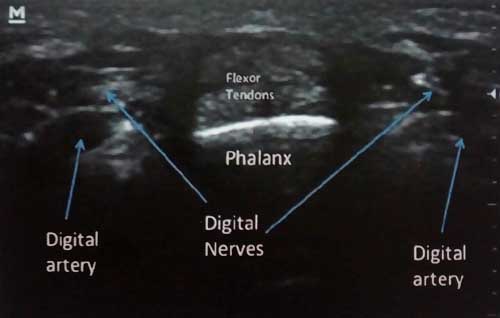

برای انجام این بلاک بیماری روی تخت می نشیند و دست مبتلا از بدن دور شده و به گونه ای قرار می گیرد که کف دست به سمت بالا باشد. محل تزریق دقیقا روی قاعده انگشت، در طرف کف دست است. پزشک با قرار دادن پروب سونوگرافی روی محل تزریق ساختار های داخلی را شناسایی می کند و تزریق را انجام می دهد.این تزریق هم جنبه درمانی و هم تشخیصی دارد.

تصویر سونوگرافی: